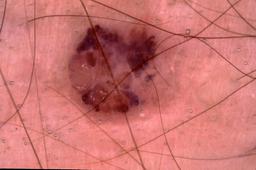

{

"age_approx": 55,

"anatom_site_general": "posterior torso",

"concomitant_biopsy": true,

"dermoscopic_type": "contact non-polarized",

"diagnosis_1": "Malignant",

"diagnosis_2": "Malignant melanocytic proliferations (Melanoma)",

"diagnosis_3": "Melanoma, NOS",

"diagnosis_confirm_type": "histopathology",

"image_type": "dermoscopic",

"lesion_id": "IL_6864076",

"melanocytic": true,

"patient_id": "IP_4659192",

"sex": "female"